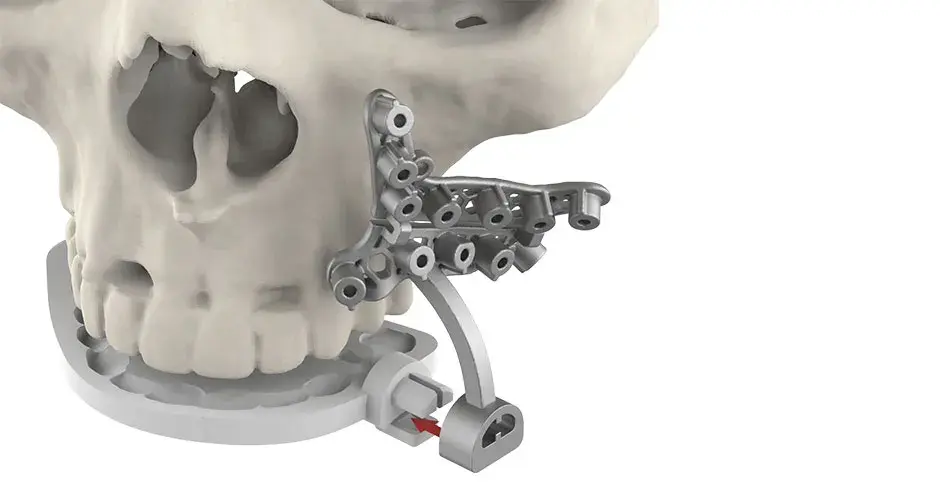

3D Systems' VSP® surgical planning solutions for craniomaxillofacial (CMF) applications received FDA clearance as a service-based approach to personalized surgery over 10 years ago.

3D Systems and Stryker Corporation have partnered to provide surgeons with best-in-class products and services for craniomaxillofacial surgeries. As a leader in personalized healthcare solutions, 3D Systems has planned and delivered devices for more than 140,000 patient-specific cases. The Stryker Craniomaxillofacial business specializes in providing patient-specific options and innovative solutions that help drive efficiencies in surgical suites. The combination of Stryker’s specialized team and advanced implants with 3D Systems' cutting-edge 3D printing technologies and expert consulting services positions both companies to provide a superior level of service to healthcare professionals who use these revolutionary solutions.